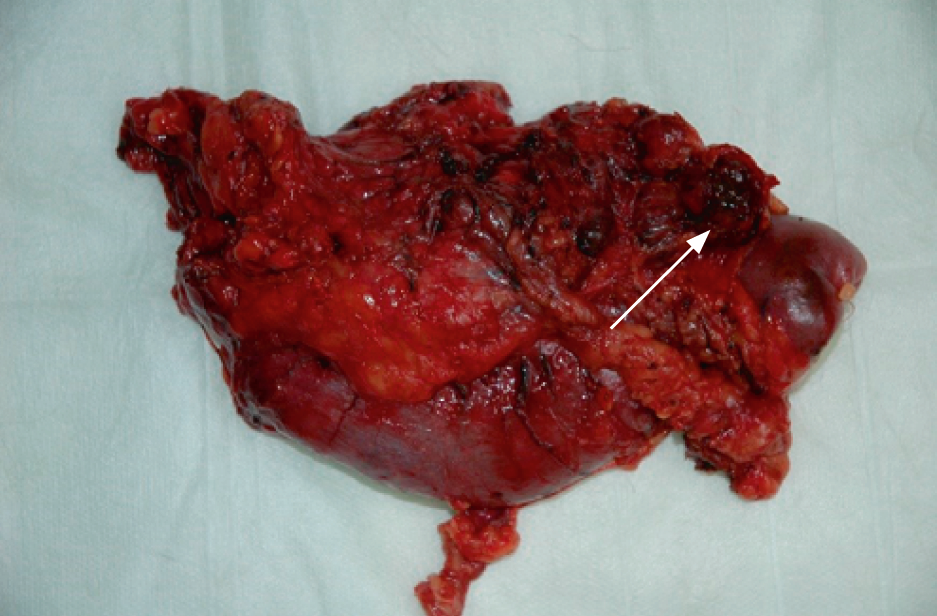

7. Fig. 4. Tumor (insulinoma) of the pancreatic head.

Subject

8. Fig. 5. Pancreatoduodenal complex, lymph nodes.